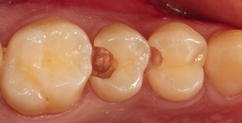

Bei der 55-jährigen Patientin imponierte eine okklusal penetrierte Sekundärkaries an dem Goldinlay an Zahn 15 (Abb. 8). Nach Aussage der Patientin war der Zahn seit ein paar Wochen aufbissempfindlich; die Vitalität war gegenüber Zahn 14 und 16 reduziert. Hieraus ergab sich die Behandlungsindikation zur Entfernung des Inlays und zur Vorbereitung einer endodontologischen Therapie. Nach der Entfernung des Inlays imponierte ein massiver Kariesbefall im gesamten Kavitätenbodenbereich (Abb. 9). Nach der Exkavation zeigten sich eine Verbindung zur Pulpa als auch diverse Infraktionslinien (Abb. 10). Die Verbindung zur Pulpa wurde interimsmäßig überkappt (TheraCal LC, Abb. 11); die Trepanation des Zahnes wurde dem Endodontologen überlassen. Vor einer endodontologischen Behandlung ist eine dichte adhäsive präendodontologische Aufbaufüllung essenziell. SDR flow+ hat die Indikation zur Aufbaufüllung in seinem Indikationsspektrum.

Der Aufbau eines solchen Zahnes mit einem Bulk-Flow-Komposit in zwei horizontalen Inkrementen (Kavitätentiefe deutlich > 4 mm) erleichtert und verkürzt selbst bei zwei Polymerisationszyklen die Gesamtversorgungsdauer im Vergleich zu einem dualhärtenden Aufbaukomposit. Hinzu kommt, dass alle dualhärtenden Aufbaukomposite keine definitiven Füllungsmaterialien sind und später entweder wieder entfernt oder komplett von einer indirekten Restauration eingefasst sein müssen. Das Bulk-Flow-Komposit hingegen ist ein definitives Füllungsmaterial, welches später – nach der endodontologischen Versorgung – als Kavitätenbodenelevation [16,23,31,34,47,60] verbleiben kann. Somit schont man mit Sicherheit Zahnhartsubstanz, wenn eine komplette Entfernung von Komposit gerade in den Tiefen des approximalen Kastens vermieden werden kann. Die Abbildung 12 zeigt den in zwei Inkrementen SDR flow+ in der Farbe A3 aufgebauten Zahn 15. Der Zahn ist so für den Endodontologen optimal vorbereitet. Die Abbildung 13 zeigt einen Ausschnitt aus der endodontologischen Diagnostik-Aufnahme und verdeutlicht die sehr gute Röntgenopazität sowie das sehr gute approximale Adaptationsverhalten.